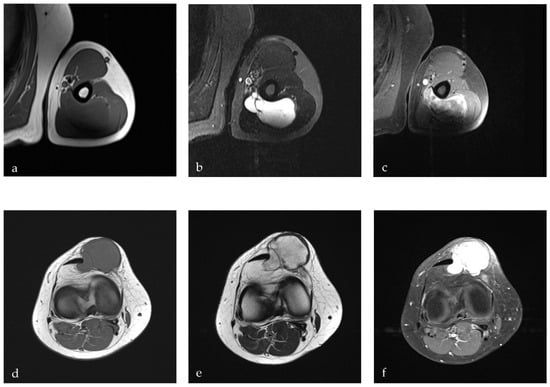

| Intramuscular Myxoma [24,37,38,39] | benign, myxoid soft tissue tumor of mesenchymal origin | hypoechoic mass with posterior acoustic enhancement | homogeneous mass; attenuation lower than muscle and higher than water; inhomogeneous, peripheral CM enhancement | homogeneous mass with hypo- to isointense signal on T1w; hyperintense signal on T2w; heterogeneous CM enhancement |